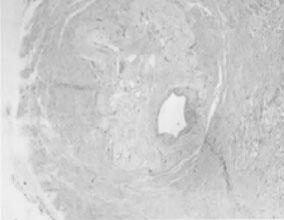

肾动脉狭窄最常见于肾动脉开口处或近端1/3血管,非开口处血管病变仅占15%~29%,肾动脉主干远端仅占5%。动脉粥样硬化引起的肾动脉狭窄主要累及大中动脉,动脉内膜粥样斑块,溃疡或血栓形成,多为双侧病变(见图5—1,图5—2)。

图5—1 肾动脉粥样硬化,管腔狭窄